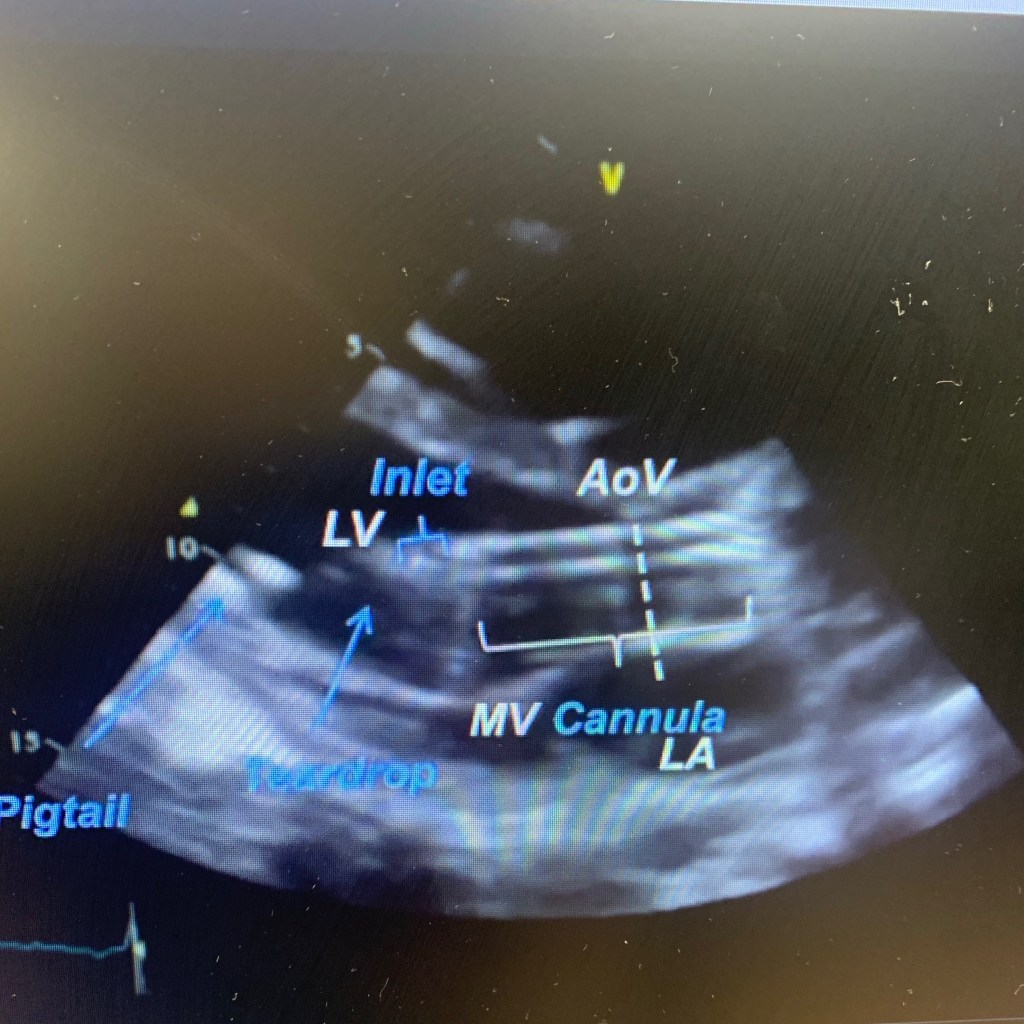

It’s hard to take pictures of either LVAD due to patients body habitus, post surgical dressings, stitches and supine position. Also, the flow is continuous. But when doing echo on LVAD patient, make sure you annotate the type, mode and pump speed. Take LV dimentions and measure EF by Simpson’s. Take pictures of aortic valve and run m-mode with reduced speed to 50mm/s, record LVAD inflow from apical conduit and use color and pulsed Doppler. And record outflow into the ascending aorta with dolor and PW. Make sure you take images (if possible) of the right heart, record any TR, visualize and take color and PW Doppler of IVC. And use color if needed to rule out any thrombus formation.

🔘 blunted flow through both cannulas – use PW/CW

Below are a few images and videos of RVAD and changes in RAMP study I did recently